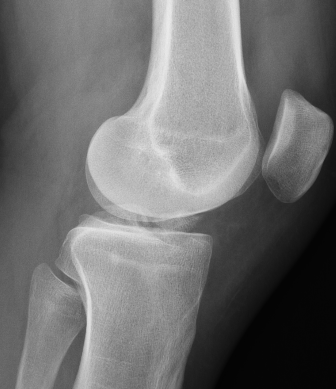

Meyers & McKeever classification

Type I: Undisplaced

Type II: Partially displaced with anterior portion hinged

Type III: Completely Displaced

Zaricznyj Type IV: Comminuted

Type II / III

Type II Type III